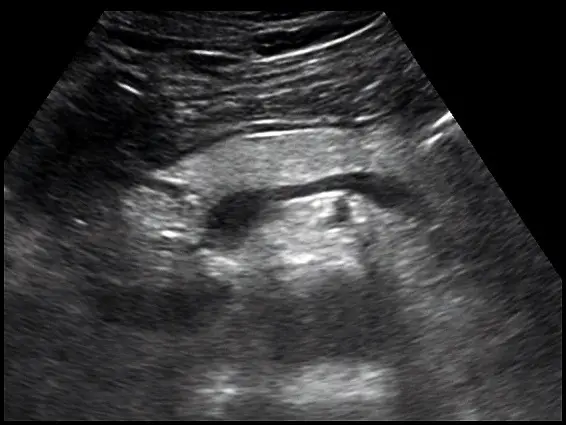

超音波掃描時,胰臟組織呈現均勻的高回音如下圖所示,最有可能的診斷為何?

提供的超音波影像為上腹部橫切面(transverse plane)。

- 影像中央可見一條無回音(anechoic)的管狀構造,為脾靜脈(splenic vein)。

- 在脾靜脈前方的實質構造即為胰臟(pancreas),包含胰體(body)與部分胰尾(tail)。

- 觀察胰臟的實質組織(parenchyma),其呈現均勻且明顯的高回音(uniformly hyperechoic,即影像上看起來非常白亮)。正常情況下,年輕人的胰臟回音應與肝臟等回音(isoechoic)或稍微偏高(slightly hyperechoic)。當整個胰臟呈現如此顯著的高回音時,最常見的原因是脂肪浸潤。

- 影像中未見局部低回音腫塊(focal hypoechoic mass)、無主胰管擴張(no pancreatic duct dilation),也無胰臟周圍積液(peripancreatic fluid),顯示這是一種瀰漫性的本質改變,而非急性發炎或惡性腫瘤。